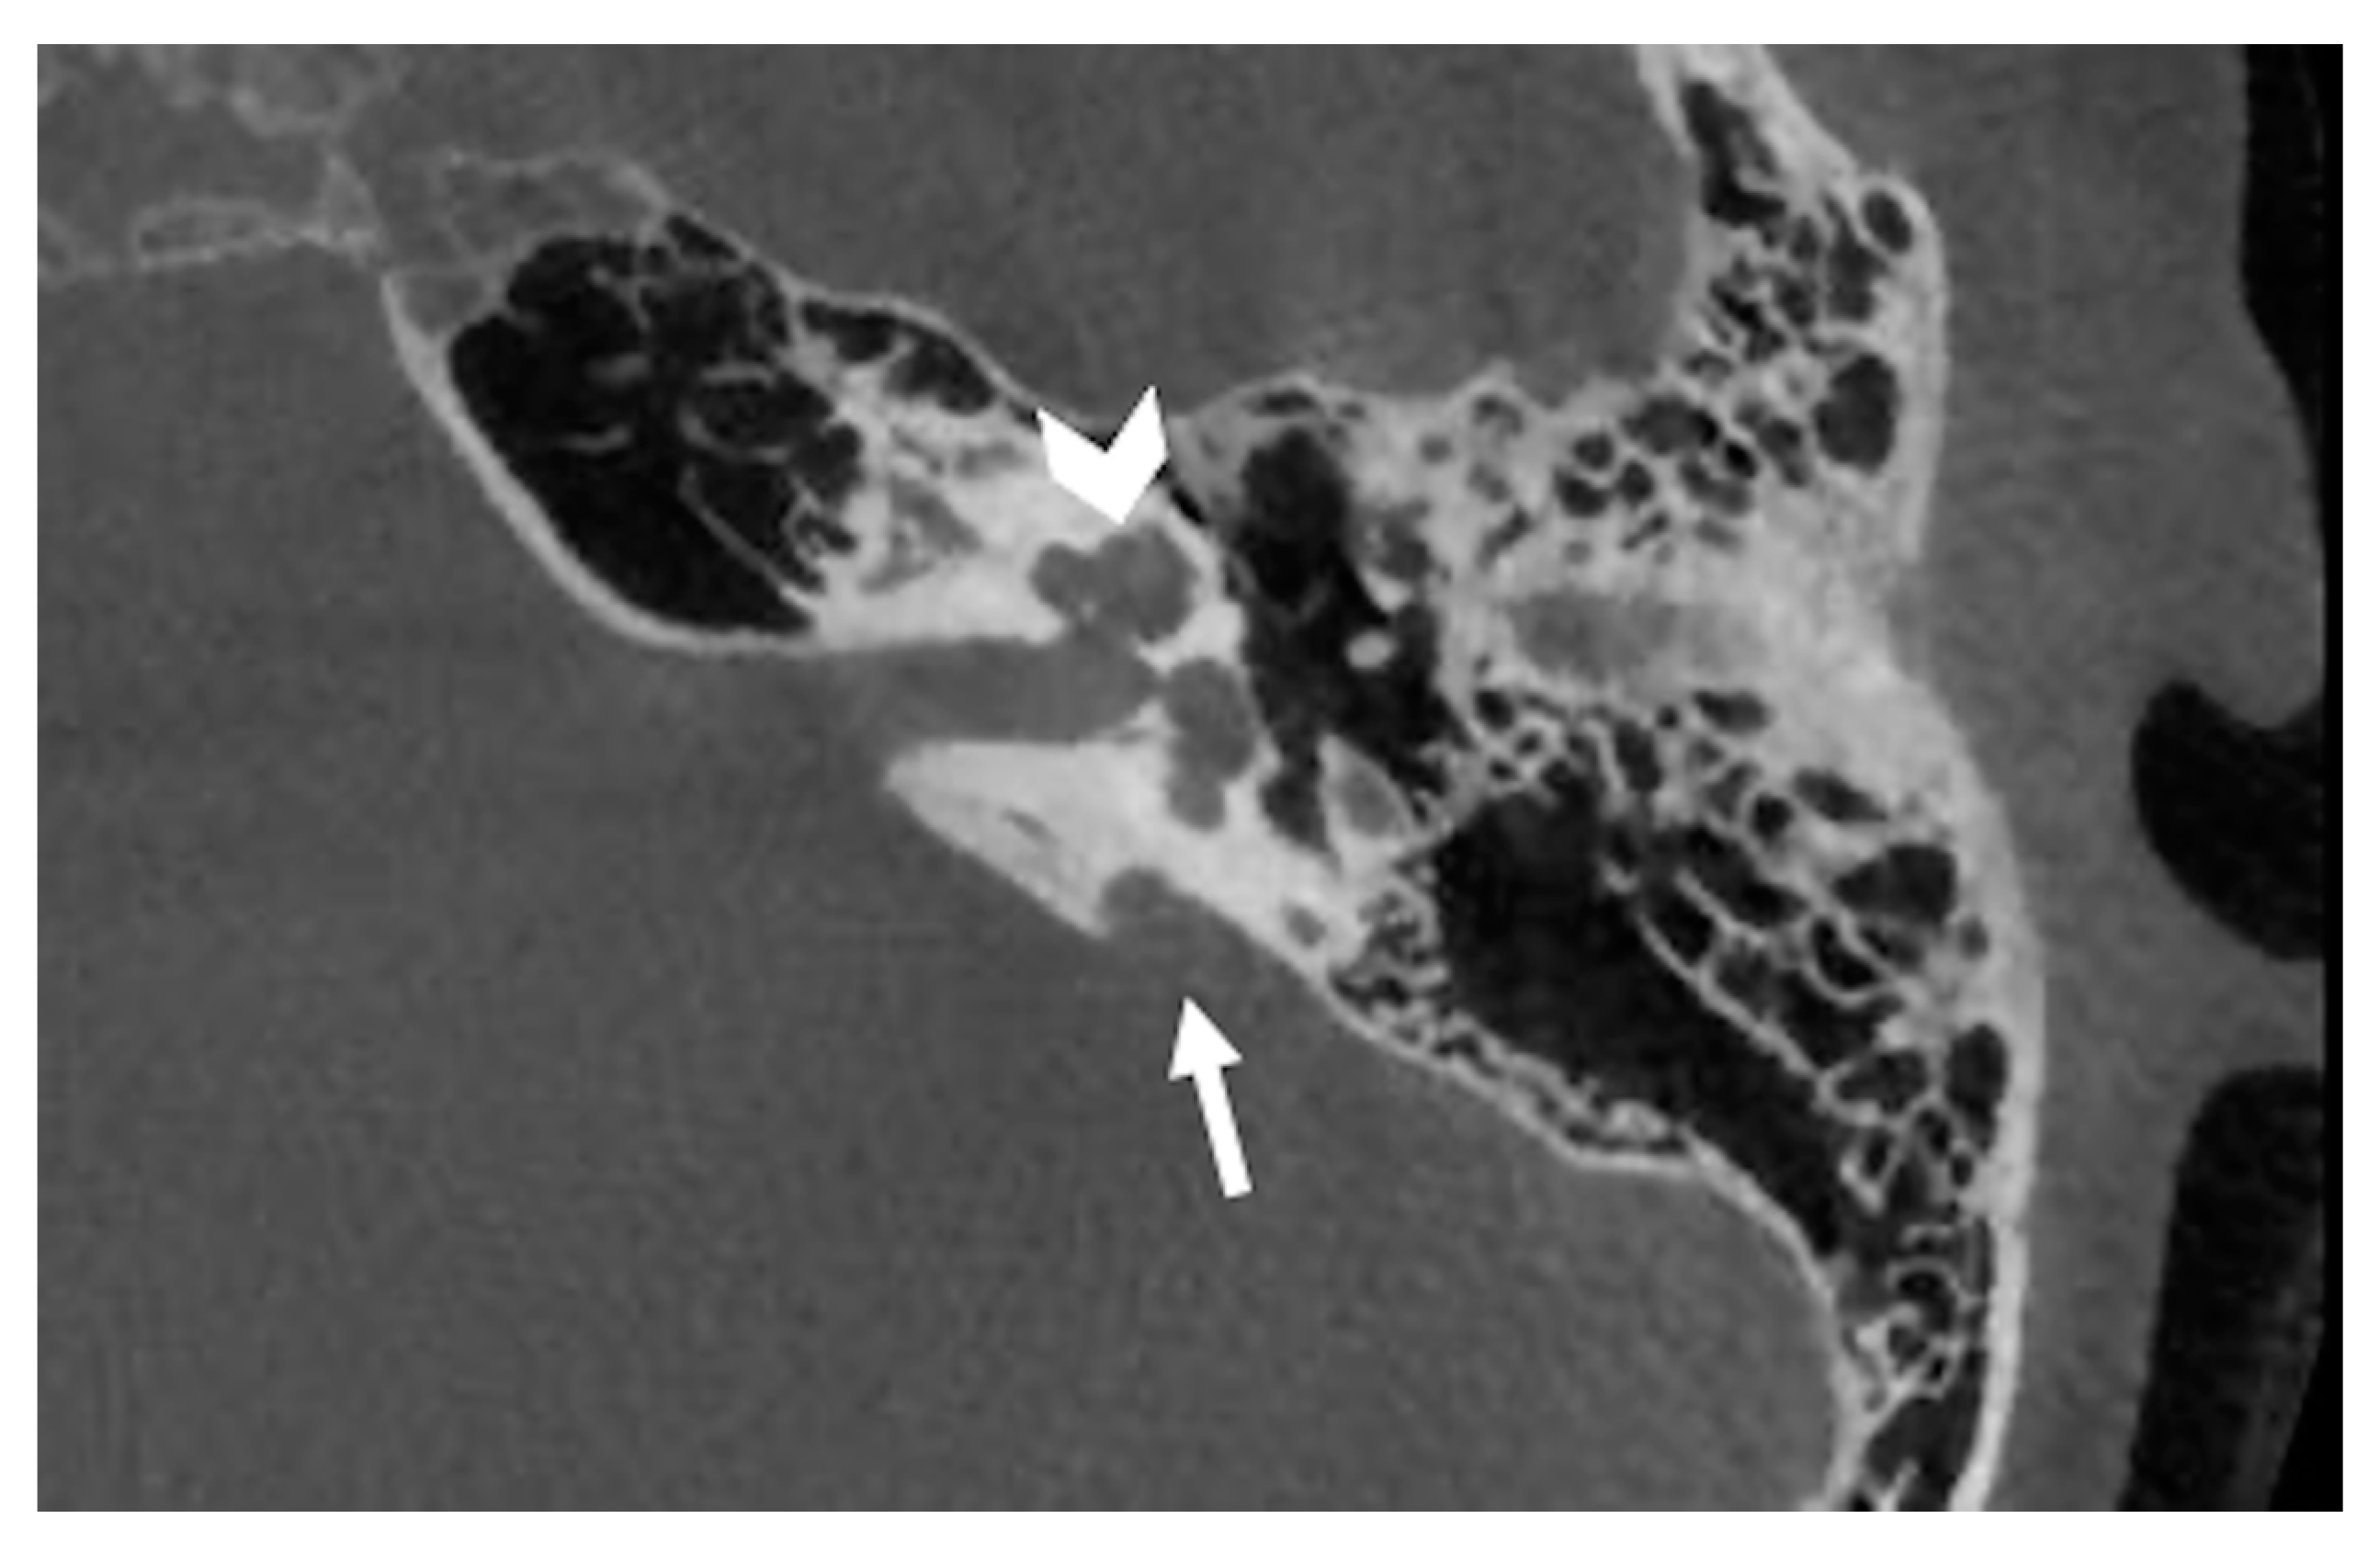

6.3. Incomplete Partition Type 3